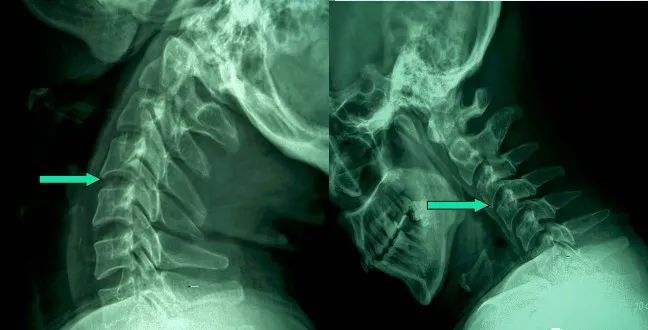

1、颈椎移位

由于颈椎关节突间关节面近乎水平位,一旦椎间盘发生退变、椎间隙即变窄,关节囊及韧带松弛,加上颈部活动时重力的影响,即可造成积累性损伤,加速颈椎退变和不稳,导致颈椎关节发生移位,使椎间孔变狭,椎管径发生改变,压迫神经根或脊髓,产生临床症状与体征。